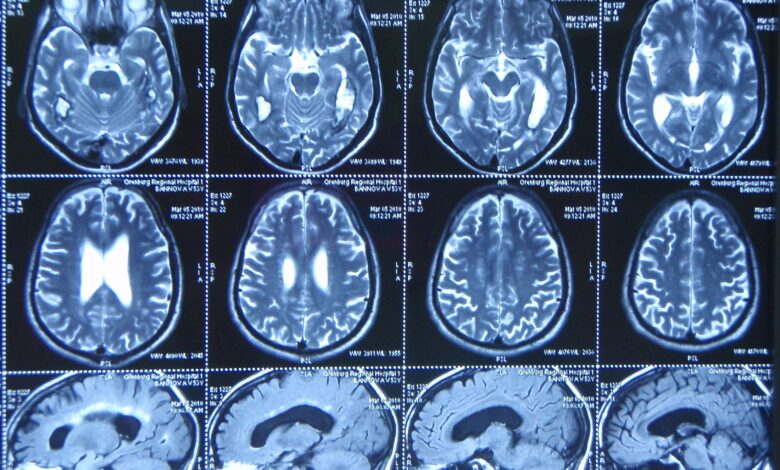

Магнитно-резонансная томография (МРТ) головного мозга с ангиографией — это современное метод исследования, позволяющее получить детальное изображение структур головного мозга и кровеносных сосудов.

Во время процедуры пациент помещается в туннель МРТ-сканера, где с помощью магнитных полей и радиоволн создается изображение мозга и сосудов.